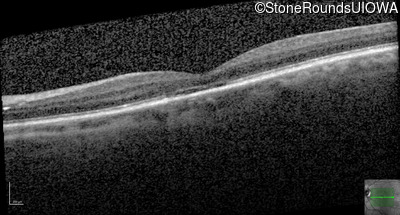

OD OS

Age at visit: 55 years

Age at visit: 56 years

Age at visit: 58 years

Age at visit: 59 years

The clinical features supporting the diagnosis of blue cone monochromacy in this patient include: stable reduced acuity, photophobia and very poor color vision since early childhood, a normal fundus appearance, normally sighted parents and three similarly affected male relatives on the maternal side of his family.